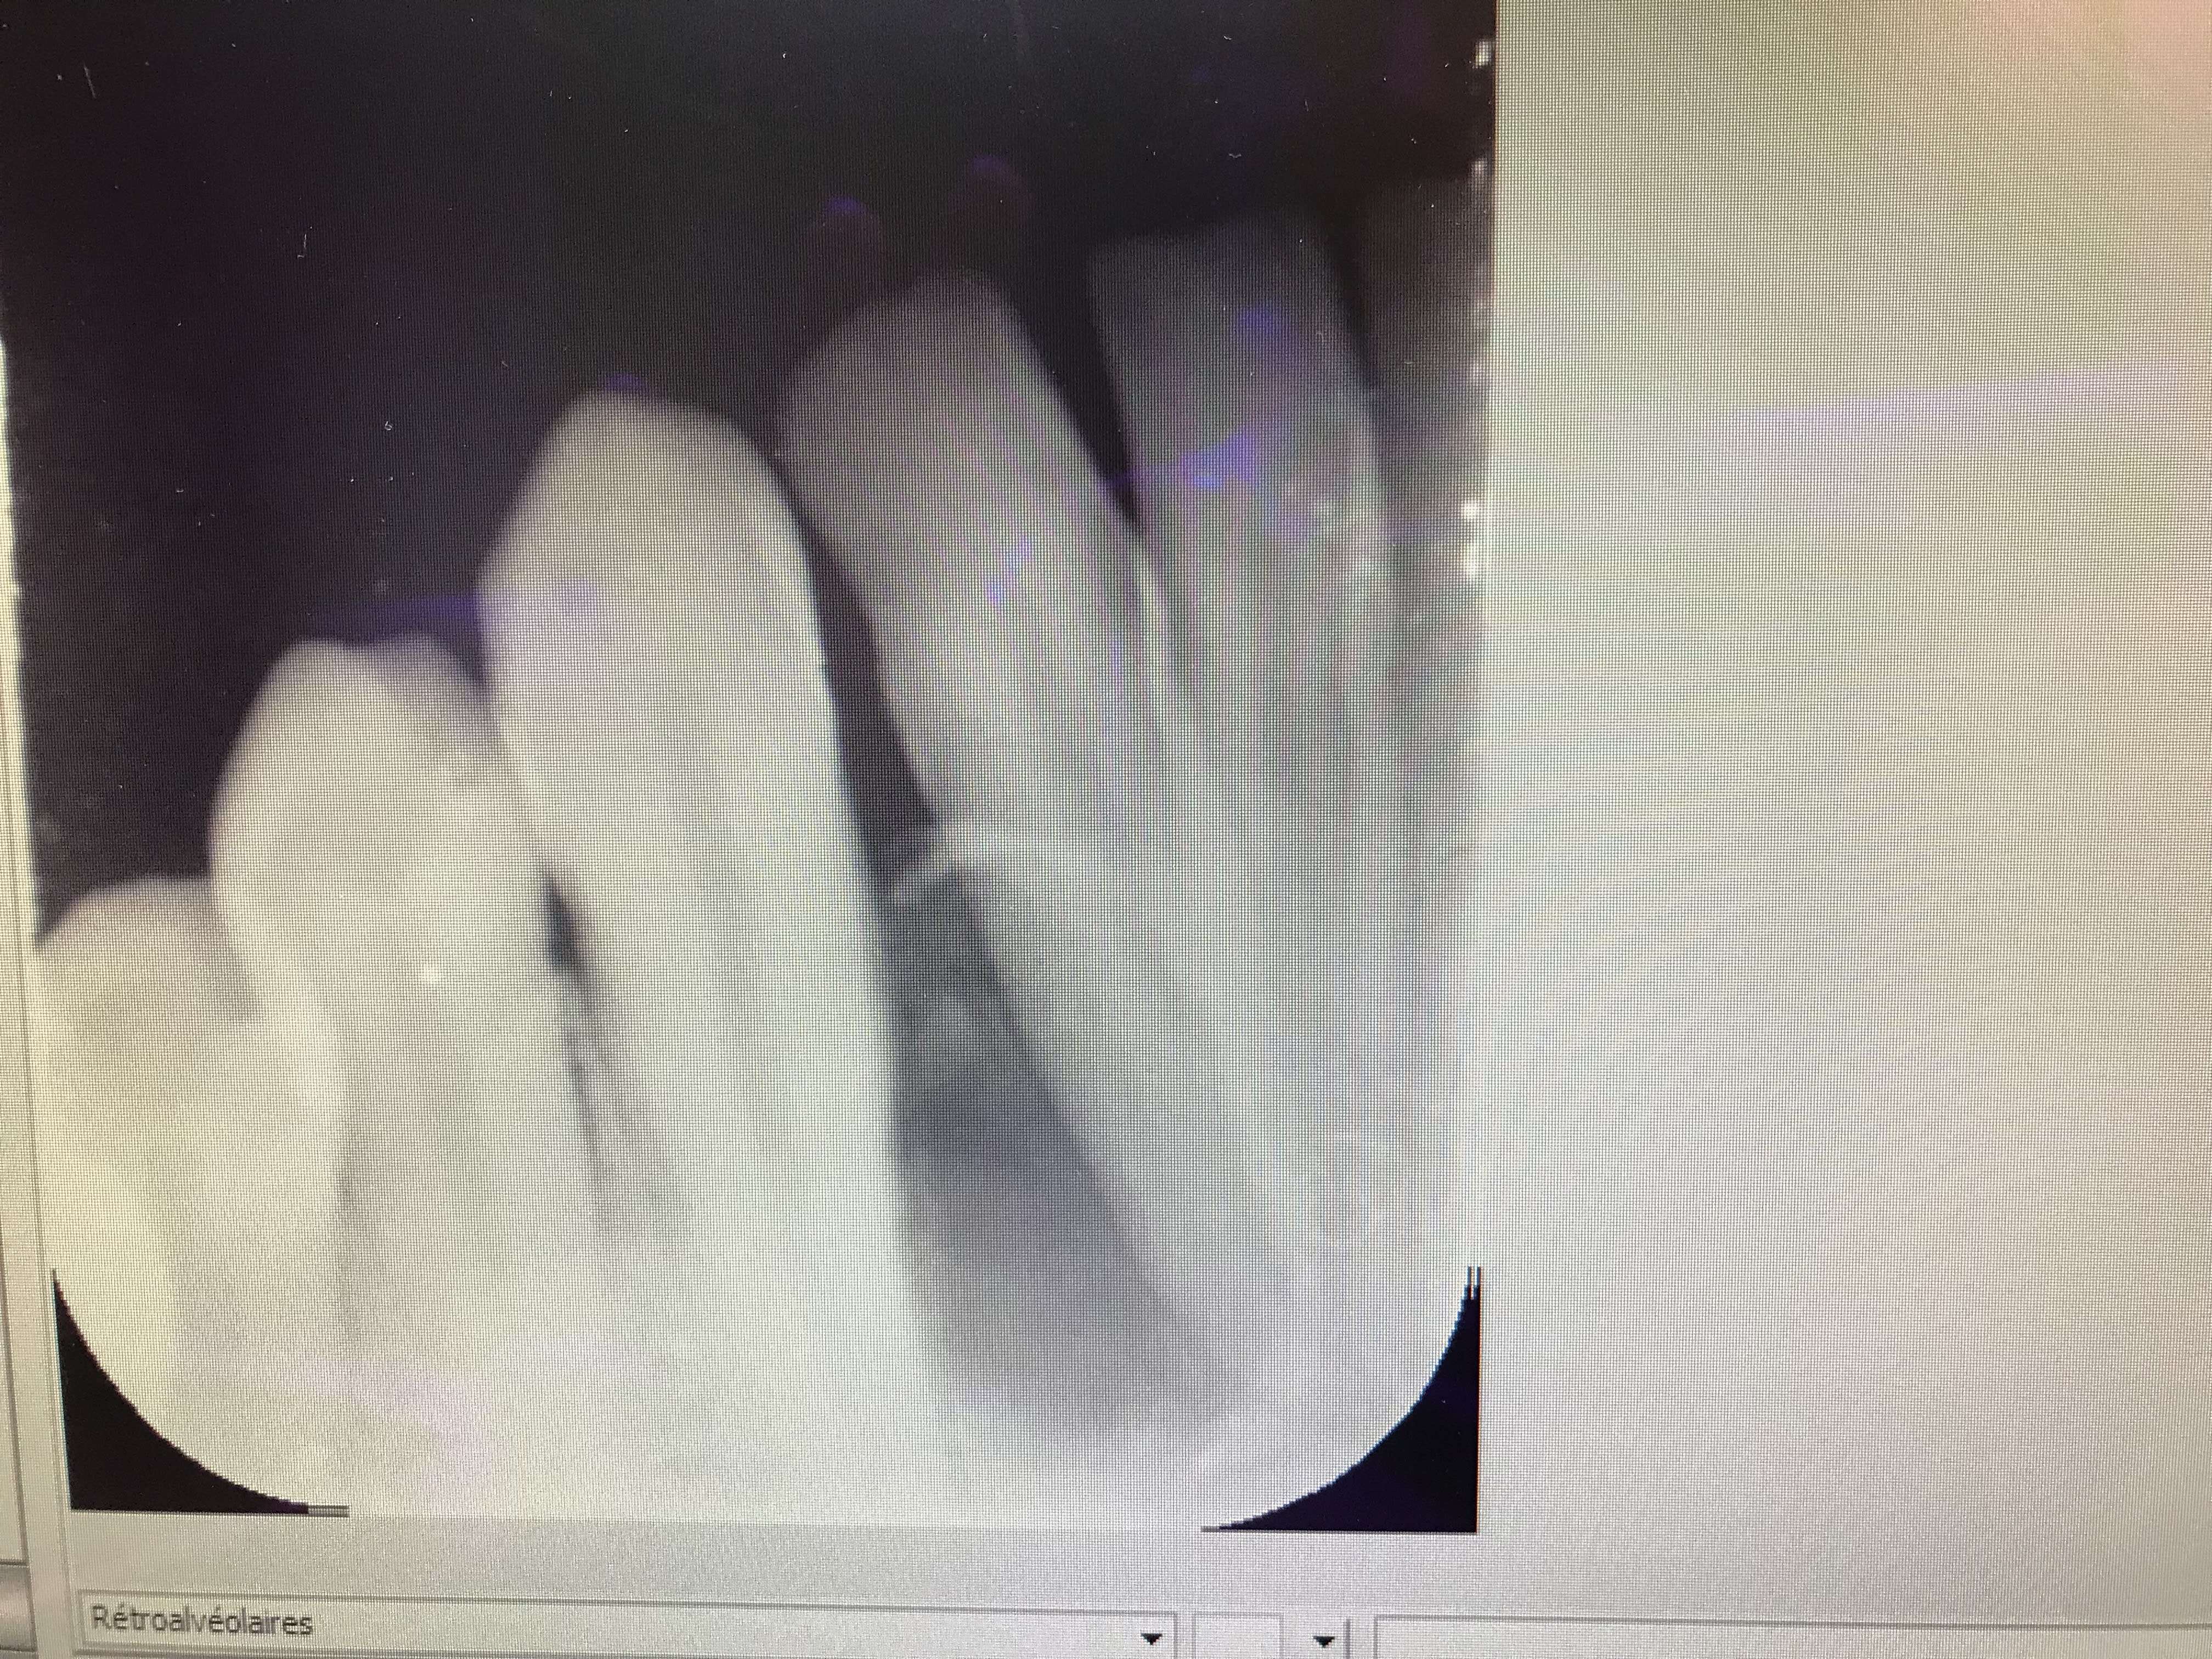

Un gros kyste entre 43 et 42?

C’est pgc qui a trouvé. T’as gagné une PPA à selles disjointes comme récompense ;))

Pour la petite histoire, il est venu au cabinet en m’expliquant qu’il avait fait une crise d’ épilepsie dans sa piscine et que depuis son incisive avait bougé. Il était persuadé que c’etait suite à un choc dans sa piscine .

Kyste parodontal latéral

D’ailleurs dans cet article ils racontent que ça a une croissance très lente. C’est faux il y a 3 mois il n’avait Absolument rien .... à croire que ça croît rapidement

Tu n'avais pas pris de radio il y a 3 mois. L'effet et la cause :-))) Un kyste latéro radiculaire ne met pas trois mois pour atteindre cette taille!

Je suis d’ accord sauf que sa dent était parfaitement droite il y a 3 mois. Ça prouve bien que ça évolue rapidement

Le kyste était peut être là il y a 3 mois . C’est certainement le cas .... sauf que il y a 3 mois les dents étaient alignées. Ce qui prouve que le kyste grossit rapidement